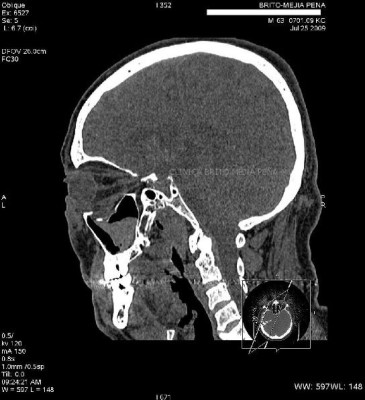

Fístula LCR axilar